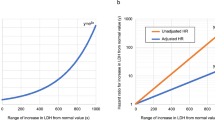

Among 269 patients for whom CT images obtained at the time of admission were available, the most frequent findings in severe cases were GGO, followed by bronchiectasis, air bronchogram, subpleural line, crazy paving pattern, consolidation, and bronchial wall thickening (Fig. 1). Abnormalities were distributed in the peripheral region, but in severe cases, they also spread to the central region, and in most cases, this was observed bilaterally (Fig. 2). While one case had pulmonary edema and another had aspiration pneumonia, all cases had lesions due to COVID-19 pneumonia; Fig. 3 shows two representative cases with such lesions on CT. In non-severe cases, GGO was observed in the peripheral region (Fig. 3a), but was also found in the central region in some patients (Fig. 3b). Elevated total scores were observed in severe cases (Fig. 4; see also Supplementary Table 1). Severe cases presented high scores in not only the lower lobes but also the upper lobes (Supplementary Table 1). The total score groups were associated with severe disease in a dose-dependent manner as shown by the increase in the crude ORs with increase in total score (Table 4, top). The OR adjusted for sex and age (aOR) showed similar results; adjusted for sex, age, and hospital size, the associations of the CT scores remained the same. In addition, when the total score was treated as a continuous rather than categorical variable, the OR increased by 1.5 (95% CI = 1.3–1.7) for every 1-point increase in total score, and increased by 1.4 (95% CI = 1.2–1.6) when adjusted for age, sex, and hospital size. In the ROC analysis of the total score, the AUC was 0.93 (95% CI = 0.89–0.98) and an optimal cut-off score of 11 was found to predict severe disease with 90.9% sensitivity and 82.2% specificity.

Among 168 cases for which chest X-ray images obtained at the time of admission were available, the common findings of severe cases included reticular-nodular opacities, cardiomegaly, and consolidation (Fig. 3c and Fig. 5). In particular, high CTR values were observed in both PA and AP views of severe cases (Fig. 6) and cardiomegaly was strongly associated with severe disease [OR = 52.1 (95% CI = 13.0–208.4); aOR for sex, age, hospital size, and patient positioning of chest X-ray = 24.6 (95% CI = 3.7–166.0)]. For cardiomegaly, a case was excluded from the calculation due to insufficient information to classify to PA or AP. Abnormalities were distributed in both lungs, in each zone, and showed a basal predominance (Fig. 7; see also Supplementary Table 2). High total scores were also observed in severe cases (Fig. 8; see also Supplementary Table 2). The total score groups were associated with severe disease in a dose-dependent manner (Table 4, bottom, crude OR), and the aOR controlling for sex and age showed similar results. In addition, adjusted for hospital size, the association remained similar between severe disease and chest X-ray score. When the total score was treated as a continuous rather than categorical variable, the OR increased by 1.2 (95% CI = 1.1–1.2) for every 1-point increase in total score, and the aOR increased by 1.1 (95% CI = 1.0–1.2), after adjustment for sex, age, and hospital size. An ROC analysis of the total score revealed that the AUC was 0.91 (95% CI = 0.86–0.97) and an optimal cut-off value of 9 predicted severe disease with 83.3% sensitivity and 84.7% specificity. Considering the presence of cardiomegaly on admission, for patients without cardiomegaly on admission, a high chest X-ray score of ≥ 9 showed a strong association with severe disease (crude OR = 44.1; 95% CI = 5.1–377.7; aOR controlling for sex, age, and hospital size = 11.7; 95% CI = 1.1–119.5). In patients with cardiomegaly on admission, a high chest X-ray score was not associated with severe disease (crude OR = 1.3; 95% CI = 0.1–20.7).

This is the first comprehensive report on the characteristics of the imaging findings on admission among laboratory-confirmed COIVD-19 patients in Japan. Older age and male sex were associated with severe disease, which was consistent with previous reports [1, 15, 16]. Abnormal signs in severe cases were mostly observed in the peripheral and basal regions; in severe cases, abnormalities were more frequently observed in the central region of both lungs. In logistic regression, adjusted for sex, age, and hospital size, a dose-dependent association between severe disease and the total chest X-ray and CT scores was found. Regarding the chest X-ray score, an optimal cut-off value of 9 points was found to predict severe disease with high sensitivity and specificity, although the sensitivity was lower than that of the CT score. Of note, adjusted for sex, age, hospital size, and radiographic patient positioning, cardiomegaly was strongly associated with severe disease.